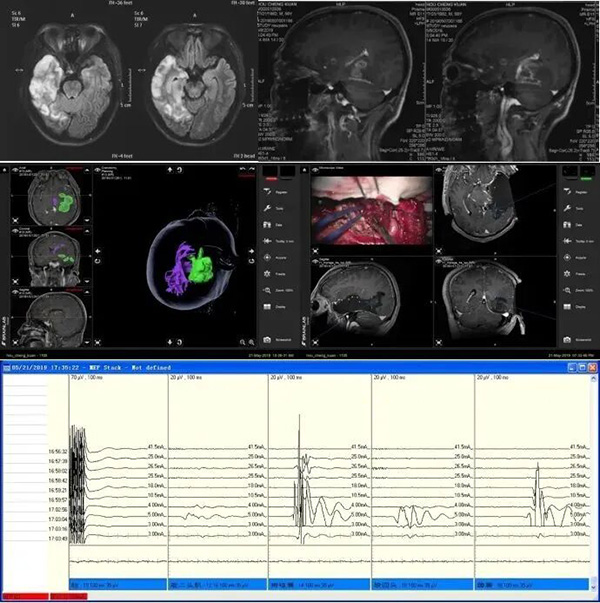

从2008年开始进行听神经瘤电生理监测,并不断改进技术,保证听神经瘤切除术后面神经功能的保留,2018年至2024年5月,共开展1000台听神经瘤手术,术后面神经解剖保留率达98.2%,功能保留率88%(House-Brackman 1–2级)。2020年开始建立了神经外科独立的听力检查室,至今累计完成听力检查4000余例;术中记录脑干听觉诱发电位(BAEP)和耳蜗神经动作电位(CNAP),精准定位听神经实际走形,并实时评估听觉传导通路的完整性,实现患者有效听力的最大化保留。利用术中核磁以及术中导航技术的优势,结合影像学技术,开展了皮层下电刺激以定位传导束与肿瘤的相对边界,保证患者术后运动和感觉功能保留。针对涉及肿瘤言区的复杂手术,我们开展术中唤醒监测技术。在涉及语言区肿瘤切除中,应用术中唤醒+语言测试+皮层电刺激综合技术,构建个体化语言功能保护方案。此外,脑肿瘤电生理监测技术还广泛应用于岩斜区肿瘤、枕骨大孔区肿瘤、鞍区肿瘤、脑干肿瘤等多个部位。针对不同肿瘤的解剖特点,监测对应受影响的颅神经及诱发电位,形成了全面、系统的电生理监测体系。

听神经瘤切除术的电生理监测技术

结合术中影像定位的皮层下电刺激技术